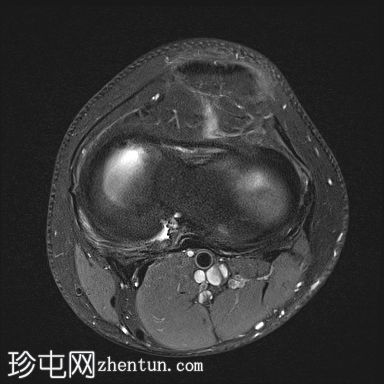

5.jpg

轴向PD

脂肪饱和度

股骨内侧髁发育不全

胫骨髁间棘发育不全

腓骨头发育不全

前交叉韧带(ACL)和后交叉韧带(PCL)发育不全

髌腱延长,低位插入。

腘绳肌腱起源异常

外侧胫骨半月板韧带增厚;与外侧韧带(LCL)连接

术后可能出现股四头肌腱改变